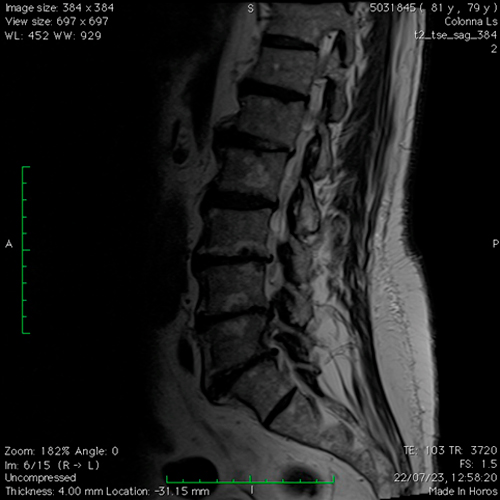

DIAGNOSI:

Paziente anziano con diverse comorbidità, affetto da stenosi lombare foraminale multilivello

Risonanza magnetica lombare pre-operatoria

Intervento chirurgico eseguito:

Introduzione di dispositivo interspinoso lombare L3-L4 per via percutanea

Radiografia post-operatoria